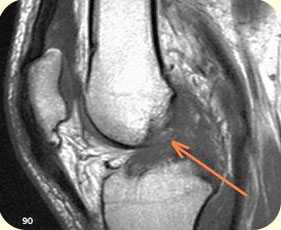

2. ЯМРТ (ядерно-магнитно-резонансная томография) Современный, высокоинформативный, безопасный метод исследования. Лучше всего подходит для определения мягкотканых повреждений: связочного аппарата, повреждений менисков, хряща и др.

разрыв крестообразных связок коленного сустава (изображение слева), разрыв заднего рога внутреннего мениска коленного сустава (изображение справа)